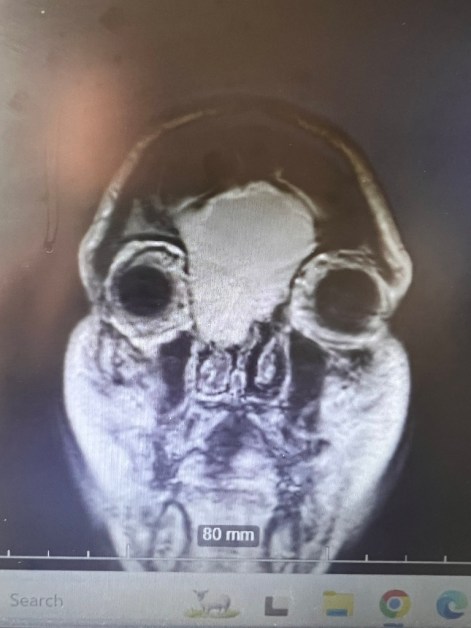

Giving Hope Through Jaw Reconstruction: Treating Ameloblastoma in Kenya

Ameloblastomas are benign but locally aggressive tumors that most often arise in the mandible (lower jaw). While they grow slowly, patients in Kenya frequently present with very large masses by the time they come for treatment — far larger than any I encountered during my surgical training in the United States. Once these tumors reach…